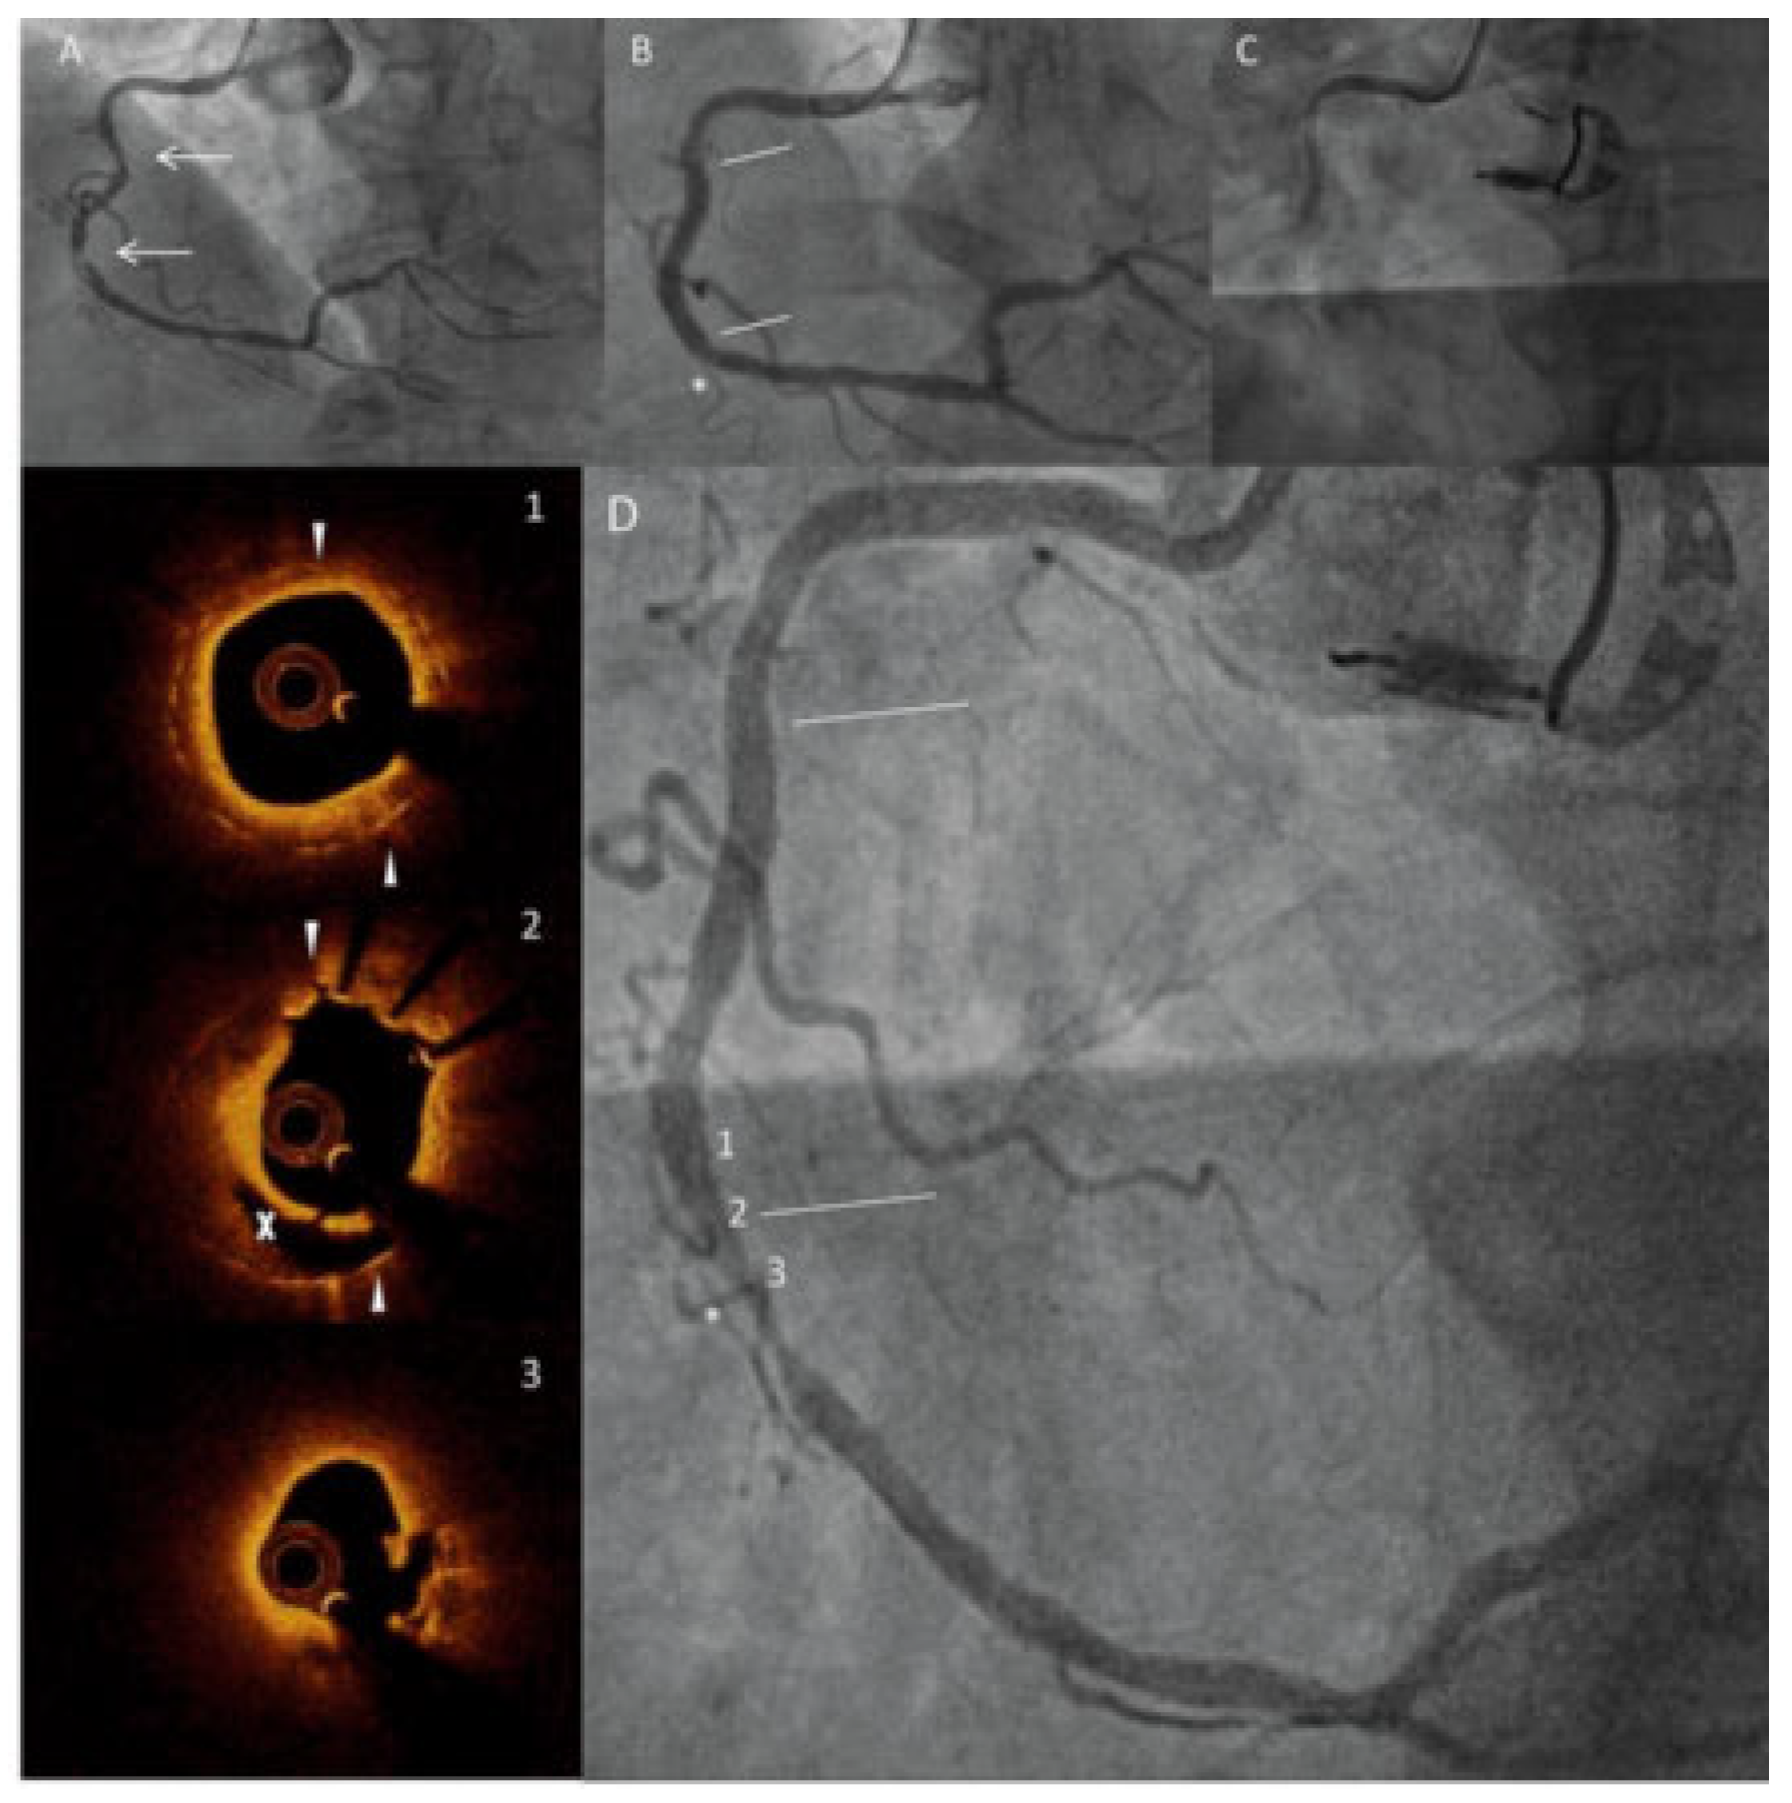

Geographic miss leading to neoatherosclerosis and very late stent thrombosis

Case description